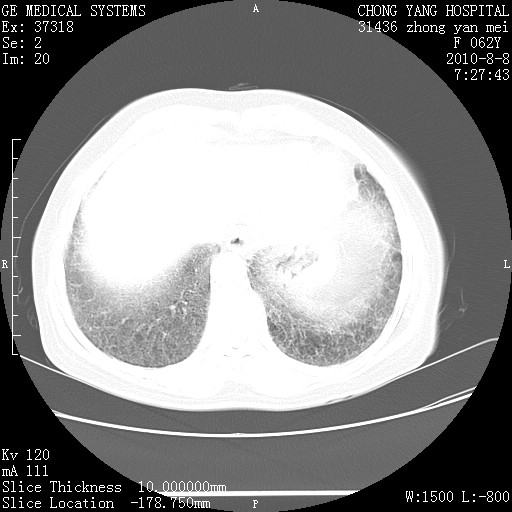

标题: CT28269:F62Y咳嗽胸痛数月。 [打印本页]

标题: CT28269:F62Y咳嗽胸痛数月。

两肺弥漫性间质纤维化伴继发性支扩。

考虑特发性肺间质纤维化

考虑两肺间质性肺炎并肺间质纤维化。

双肺间质纤维化合并感染、肺气肿

双肺间质纤维化

两肺间质纤维化并牵拉性细支气管扩张。

考虑两肺间质性肺炎并肺间质纤维化,肺气囊形成。

两肺间质改变,纵隔淋巴结肿大,需要考虑结节病的可能。